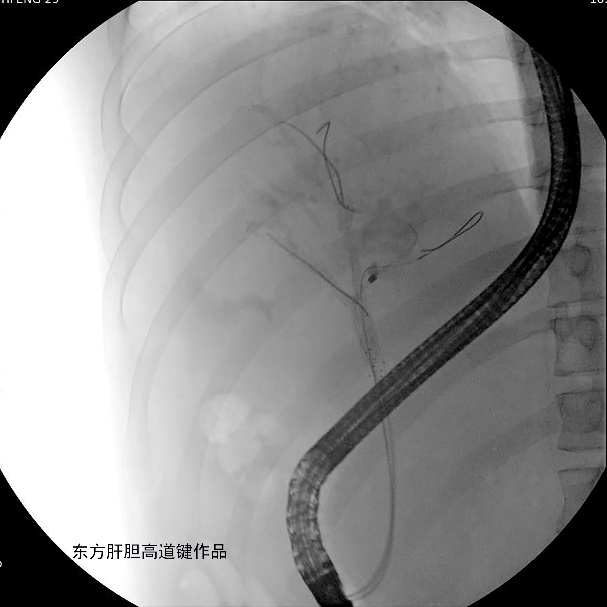

为解决胆道梗阻,于2022年3月1日行ERCP。

图A:胆总管造影见胆总管未见异常,肝门胆管细线样狭窄,累及肝总管、分叉、右前、左内及左外肝内胆管,各胆管分支间通而不畅;

图B:两根导丝分别超选进入右前及左内肝内胆管;左右肝内胆管各抽得白胆汁5ml与15ml,标本送培养;

图C:第三根导丝超选进入左外侧肝内胆管;